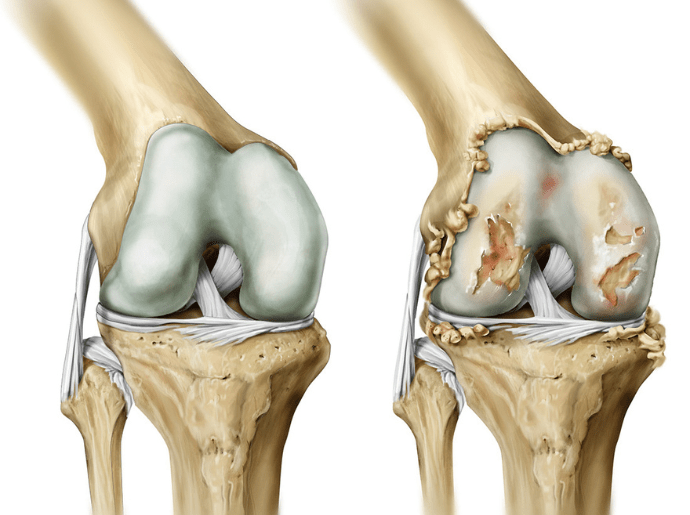

- Desgaste da cartilagem: a cartilagem articular é uma estrutura que permite o movimento suave das articulações. Com a artrose, essa cartilagem diminui em espessura e elasticidade.

- Formação de osteófitos: também conhecidos como esporões, os osteófitos são crescimentos ósseos que se formam nas bordas das articulações, podendo ocasionar dor e rigidez.

- Mudanças na estrutura óssea: o osso abaixo da cartilagem pode endurecer e formar cistos, resultando em desconforto e dor.